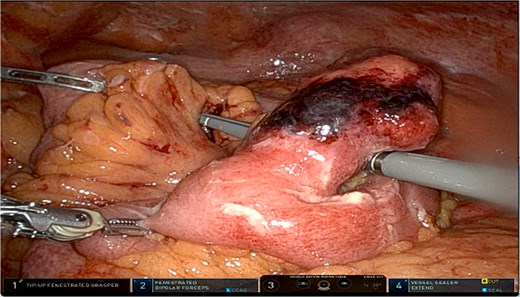

A robotic-assisted laparoscopic small bowel resection was performed using the da Vinci robotic system (Intuitive, Sunnyvale, CA). Eight mm ports were placed in the left upper quadrant at Palmer point, epigastrium, and left mid-axillary line at the level of the pelvis and a 12 mm port at the left mid-axillary line at the level of the umbilicus. Upon entry, purulent fluid, peritonitis, interloop adhesions, and abscesses were identified (Fig. 2). After adhesiolysis, the inflamed segment was isolated and resected. A stapled, side-to-side isoperistaltic anastomosis was performed. Blood supply was confirmed by near-infrared imaging with indocyanine green. Abscesses were drained, and the specimen was removed. Pathology of the specimen showed a segment of outpouching small intestinal mucosa with marked transmural acute inflammatory infiltrate, stricturing, mucosal denudation, and fibrinopurulent serosal adhesions, consistent with Meckel diverticulum.

Patients with Meckel diverticulitis typically present with right lower quadrant pain, fever, and leukocytosis. Additionally, CT imaging reveals a blind-ended pouch with mural thickness, mesenteric inflammation, or air-fluid levels [8]. In our patient, CT findings were suggestive of acute Meckel diverticulitis but did not indicate perforation or abscess formation. However, laparoscopy revealed purulent peritonitis and abscesses, confirming the presence of complicated diverticulitis with probable perforation.